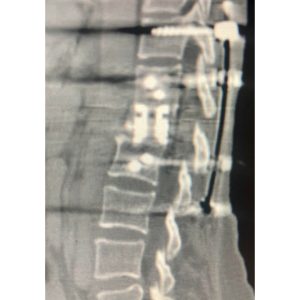

She was taken to surgery about 4 1/2 years ago and the entire L1 vertebrae and tumor was surgically removed from the front and back with the help of a vascular surgeon. I had to place extensive hardware from the front and back to support the missing vertebrae. She recovered well. Recent CT scans showed no further cancer in the spine. (Photos 3-5.)